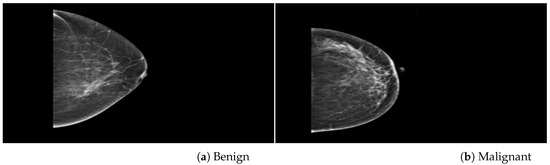

Databases

| Mammogram Label | Category | Images | Dataset |

| Benign (0) | Original | 425 | PINUM |

| Malignant (1) | Original | 152 | PINUM |

| Benign (0) | AD ROIs | 75 | PINUM |

| Malignant (1) | AD ROIs | 75 | PINUM |

| Benign (0) | Original | 1740 | CBIS-DDSM |

| Malignant (1) | Original | 1828 | CBIS-DDSM |

| Benign (0) | AD ROIs | 100 | CBIS-DDSM |

| Malignant (1) | AD ROIs | 100 | CBIS-DDSM |

| Benign (0) | Original | 2500 | DDSM |

| Malignant (1) | Original | 3000 | DDSM |

| Benign (0) | AD ROIs | 100 | DDSM |

| Malignant (1) | AD ROIs | 100 | DDSM |